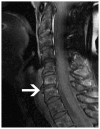

Cross-sectional imaging plays an important role in the evaluation of the retropharyngeal space (RPS) and the prevertebral space (PVS). Because of their deep location within the neck, lesions arising within these spaces are difficult, if not impossible, to evaluate on clinical examination. This article details the cross-sectional anatomy and imaging appearances of primary and secondary diseases involving the RPS and PVS, including metastasis and spread from adjacent spaces. The role of image-guided biopsy is also discussed.